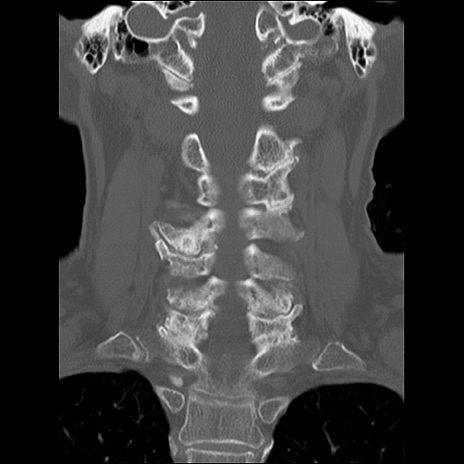

症例48 頚椎CT(冠状断像)

頚椎CT